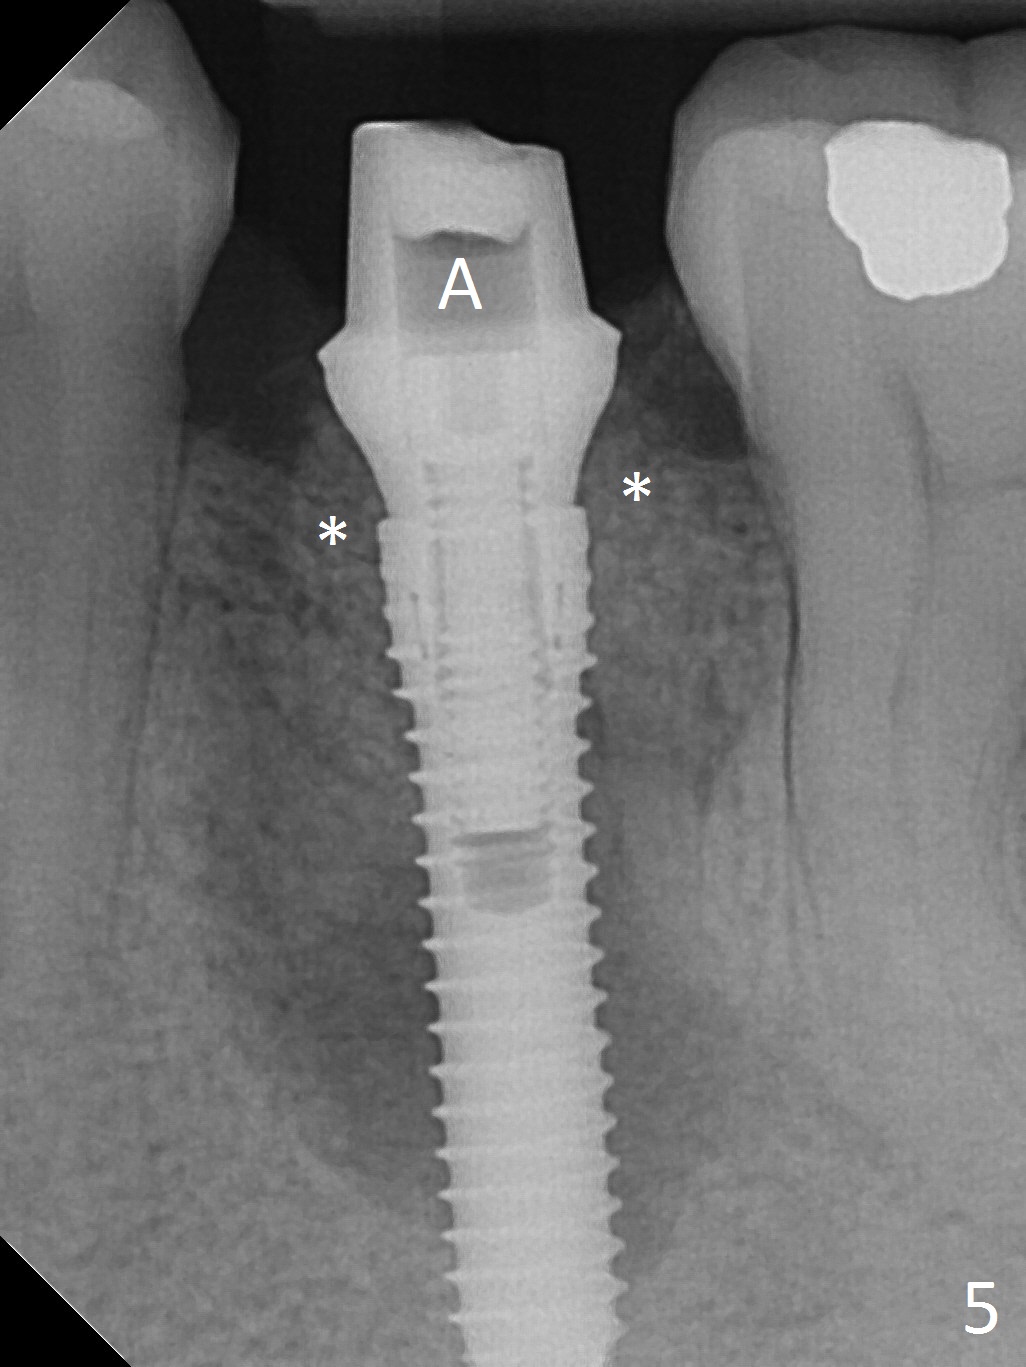

Extraction of the lower left 2nd premolar with vertical fracture (Fig.1,2 >) is easy because of peri-radicular radiolucency.  The apical end of the osteotomy is not shown with a 2 mm pilot drill (Fig.3) or a 3.8x18 mm implant (Fig.4) in place.  It appears that the implant is not placed deep enough.  Following 3-4 more turns of the implant and placement of a 5.5x4(3) mm abutment (Fig.5 A), allograft is placed (*).  A postop panoramic X-ray is taken (Fig.6); the osteotomy could have been deepened to reduce the possibility of periimplantitis.  Retrospectively, the panoramic X-ray should be taken after use of the pilot drill. The bone around the implant appears to have regenerated 4 months postop (Fig.7,8).  Bone density appears to continue increasing 9 months postop (i.e., 4.5 months post cementation, Fig.9).  Bone loss is minimal 2 years post cementation (Fig.10).